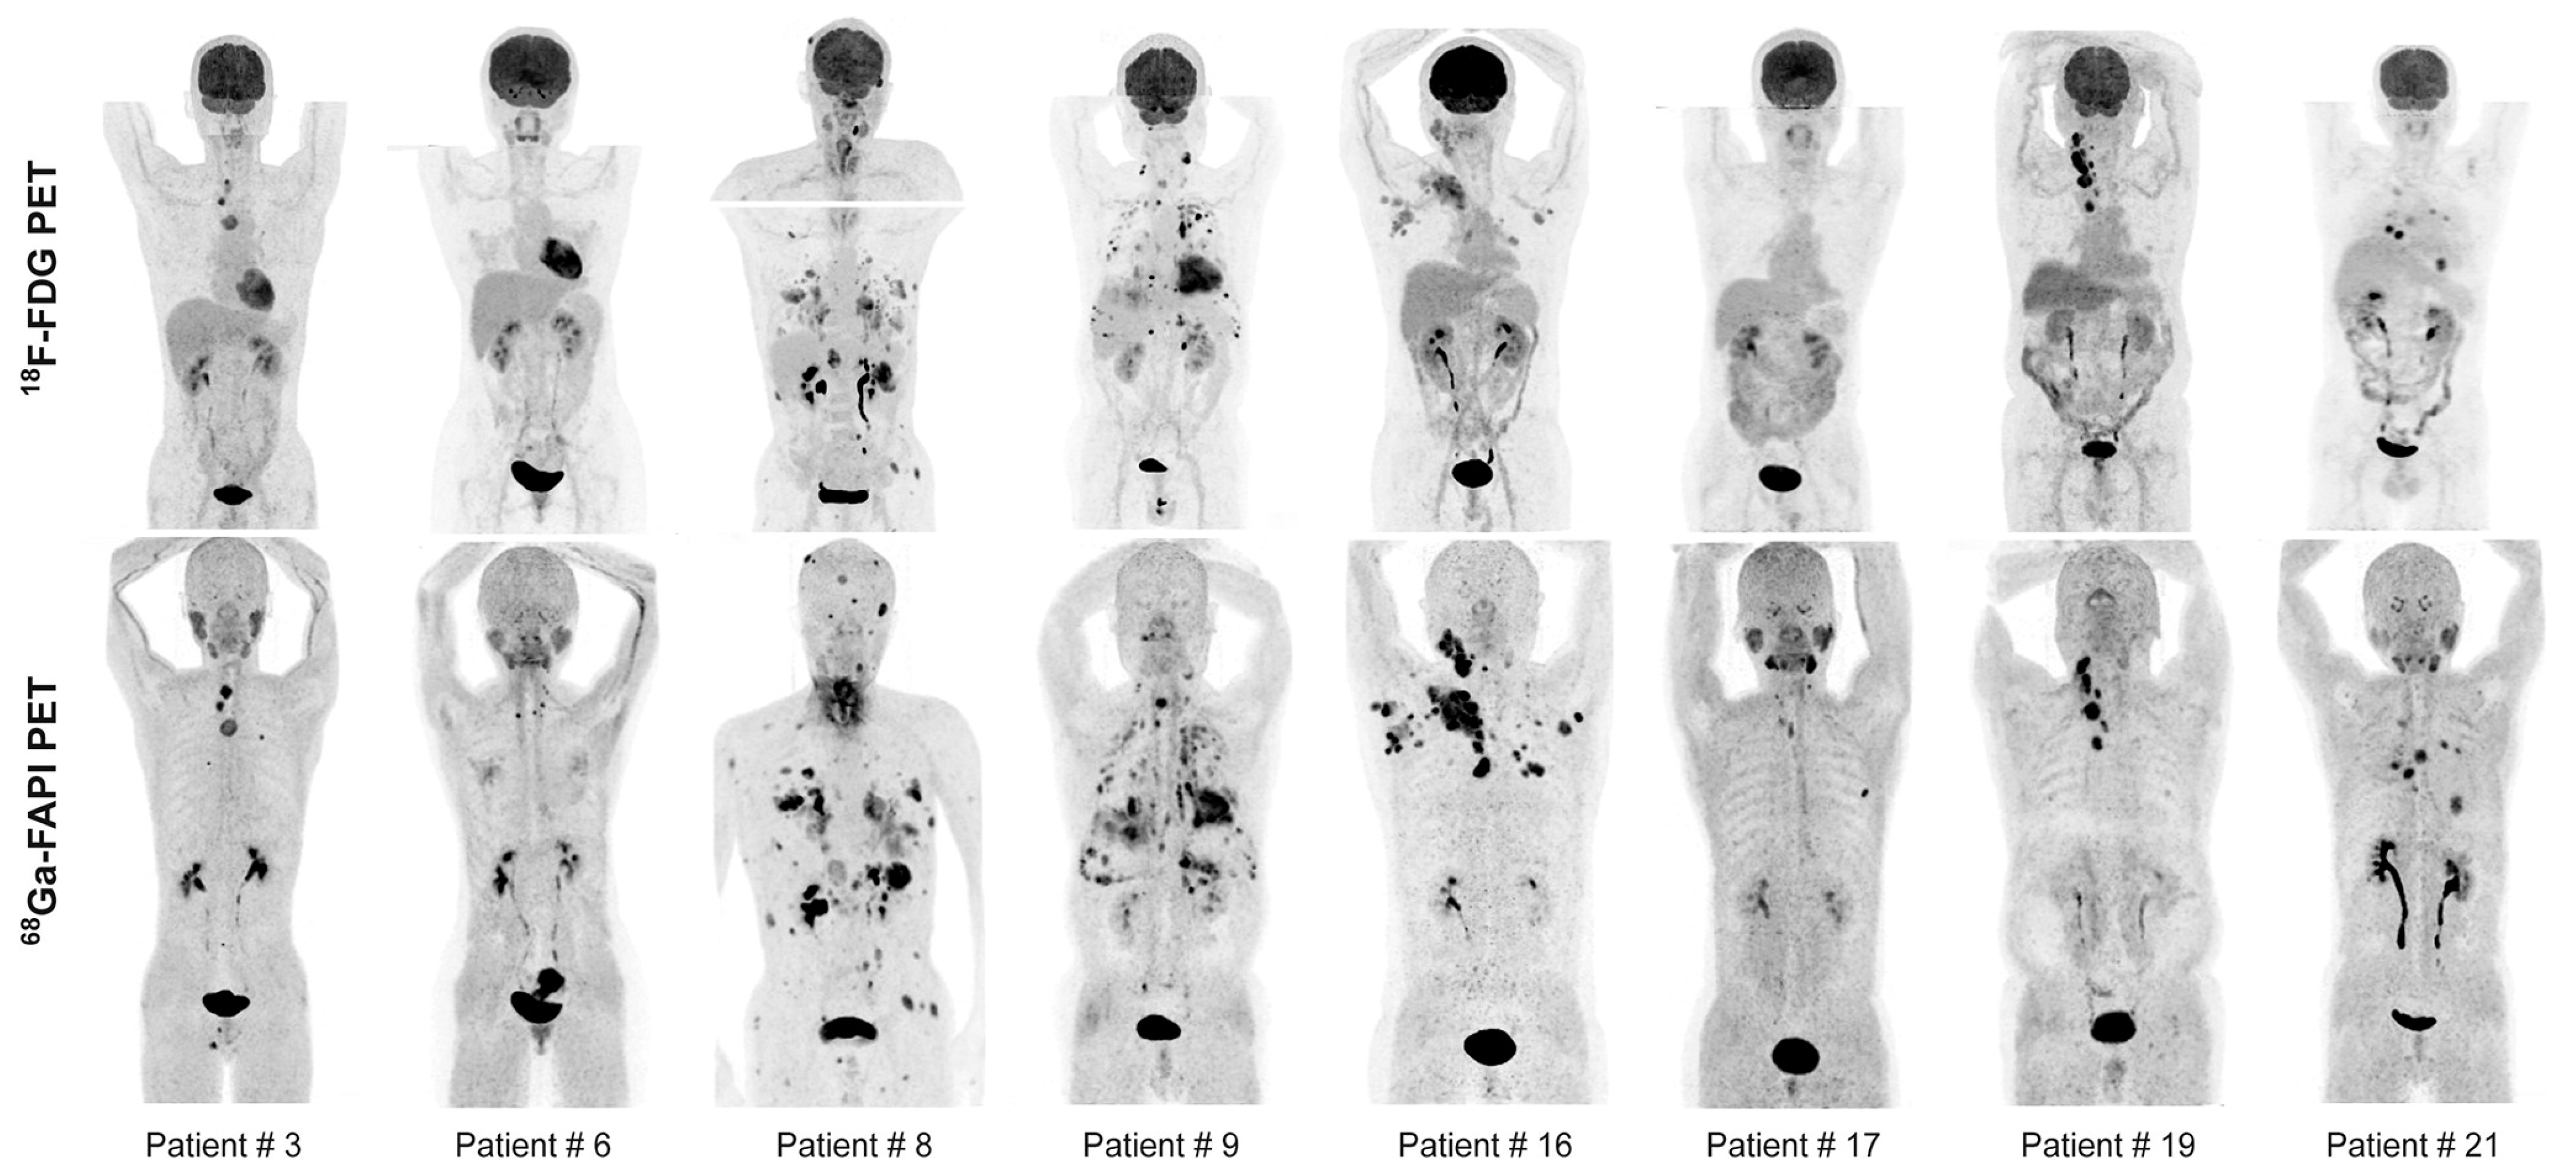

- Fu, H.; Wu, J.; Huang, J.; Sun, L.; Wu, H.; Guo, W.; Qiu, S.; Chen, H. 68Ga Fibroblast Activation Protein Inhibitor PET/CT in the Detection of Metastatic Thyroid Cancer: Comparison with 18F-FDG PET/CT. Radiology 2022, 304, 397–405. [Google Scholar] [CrossRef] [PubMed]